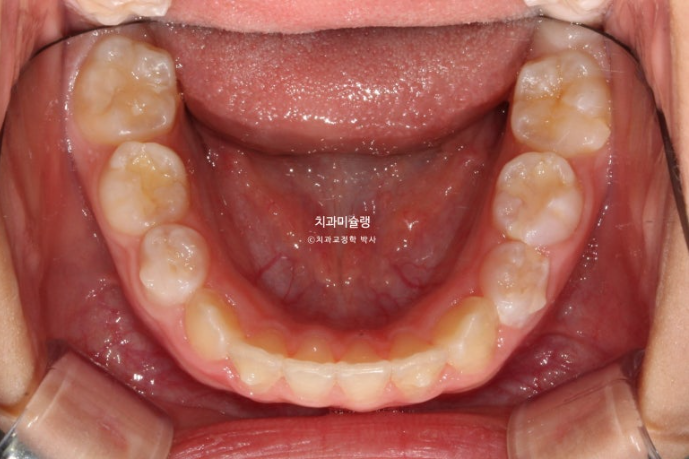

25.11

중심선은 잘 맞고

유치 한 개 빼고 나머지 치아들은 전부 영구치로, 교합이 거의 완성되었습니다.

결과가 성인교정 2차교정에 준하는 만큼 유지장치도 성인과 똑같이 들어갑니다.

파란화살표는 마지막 남은 유치입니다.

이 유치마저 빠지고 모든 영구치가 올라오면 비베라 제작에 들어갈 예정입니다.